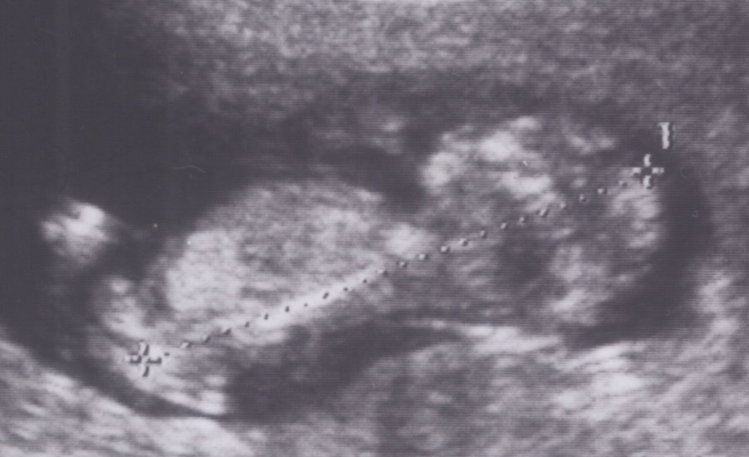

2007-05-12 八周 尺寸 - 1.87 cm

胚胎的心跳每分鐘 140—150下.是母親心跳的兩倍。醫生不斷告訴我們這才是正常的喔!!! 小寶寶很健康.....

懷孕到了第八周 而且聽到心跳 這時醫院就會給妳媽媽手冊 健保也開始承認這個小孩 並且提供 10 次的產檢給付 如果你像我們這樣 想到就會忍不住去醫院看一下寶寶 到時候 超過 10 次的部分 就多付掛號費即可 laughing

這是一個人類胚胎第8周時在子宮內的照片

第八周:此時胚胎快速的成長,胚胎長約2釐米。孕婦極其疲乏,嗜睡……(小豬頭還沒懷孕前就嗜睡了 pig )。

四肢發育大致完成,胚胎內人形已隱約可見。胎兒眼晴有一層薄薄的眼皮,外耳及嘴巴的輪廓形成。心臟血管系統發展更周全。

附加檔案 小小惡魔-20070512-心跳-web.jpg (17385 bytes) (下載次數: 6083) (小小惡魔用生命打招呼-心跳圖)